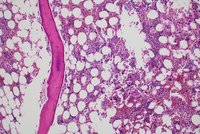

Panel A, 10X: Focal area of epithelioid cells in bone marrow core biopsy